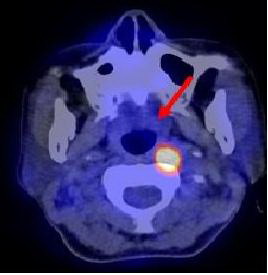

Hình 1: Hình ảnh PET tổng thể cho thấy các tổn thương tăng hấp thu

FDG bất thường tại các vị trí mũi tên

Kết quả PET/CT: tổn thương tăng hấp thu FDG mạnh tại vòm họng bên trái, max SUV=11,8, các tổn thương di căn hạch tại vùng cổ bên phải và bên trái.

Trong khi đó kết quả nội soi vòm họng và CT không phát hiện thấy tổn thương u nguyên phát (CT-) bởi vì tổn thương ở mức độ chưa xâm lấn ra bề mặt niêm mạc vòm họng và mà mắt chưa thể nhận thấy được  qua  nội soi, CT...

Dựa vào các kết quả trên, bệnh nhân được chẩn đoán là ung thư vòm họng di căn hạch cổ hai bên. Đồng thời đánh giá được giai đoạn bệnh của bệnh nhân là T1N2M0, kế hoạch điều trị tiếp theo là xạ trị phối hợp hoá trị.